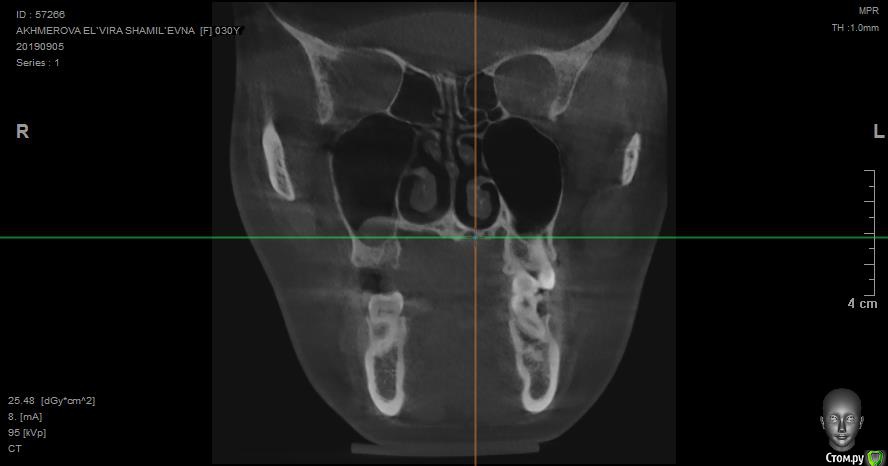

jelly Опубликовано 8 октября, 2019 Поделиться Опубликовано 8 октября, 2019 Добрый день! Посмотрите пожалуйста снимок, верхняя шестерка была удалена вместе с кистой еще в июне, до сих пор с этой стороны тянущая боль, отдающая в висок, шею и лицо. Один из лоров мне сказал, что там в одном месте есть изменения в кости. Подскажите пожалуйста, что делать дальше? Ссылка на снимки кт: https://disk.yandex.ru/client/disk/%D0%9A%D0%A2 Ссылка на комментарий

jelly Опубликовано 8 октября, 2019 Автор Поделиться Опубликовано 8 октября, 2019 КТ после удаления через 2,5 месяца сделано Ссылка на комментарий

jelly Опубликовано 9 октября, 2019 Автор Поделиться Опубликовано 9 октября, 2019 Подойдет такой снимок? Ссылка на комментарий

Irouil Опубликовано 9 октября, 2019 Поделиться Опубликовано 9 октября, 2019 Судя по всему растёт резидуальная киста. Надо удалять Ссылка на комментарий